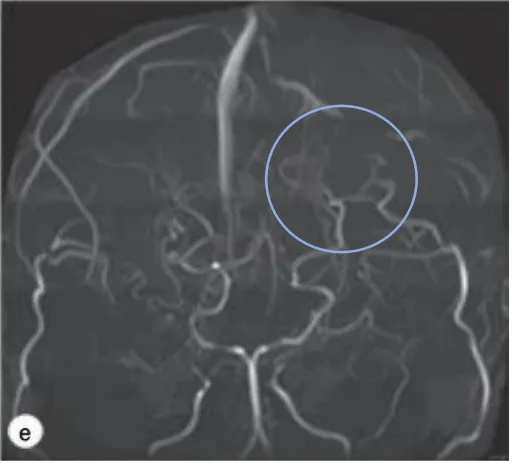

一开始手术后一个月,在对侧进行了同样的手术。这些手术均未导致高灌注综合征。双侧手术后,每6个月进行一次MRI复查。半年后,经随访DSA证实,侧支血循环明显好转,基底神经节中的烟雾血管减少。在脑XeCT检查中,两侧的脑血流量(CBF)也充分增加和好转。

图2.脑CTA显示一次搭桥术后显示良好的血管网络和基底烟雾血管消失,双侧脑血流得到改进。

直接和间接搭桥手术均有助于好转基底神经节的脑血流量和病灶烟雾血管的消退。据报道,如果搭桥手术成功,术后3-4个月烟雾血管消失或消退。也有研究显示,在成人出血性烟雾患者中,由于吻合的血管提供了侧支通路的作用,搭桥手术后再出血率下降,脆弱的烟雾血管逐渐消退。然而,在这项病例中,这名患儿术后一年半双侧发现一个小的局限性血肿。

在我们的病例中,在血管重建手术半年复查DSA显示烟雾血管消退(图2),但发现血肿扩大后重复DSA显示基底神经节毛细血管再增生。实际上,CD34/EVG染色的病理标本显示有大量的微血管。